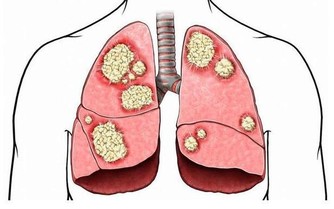

① 肝臟受損。喝酒過度,容易使脂肪堆積在肝臟,損傷肝細胞,甚至誘發脂肪肝。